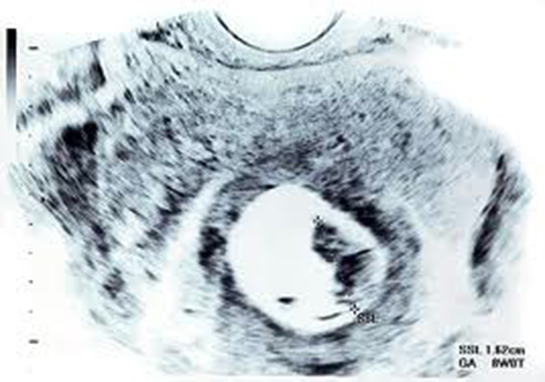

Peki, hamileliğin 8. haftasında genital tüberkül açısına bakarak cinsiyet tahmini yapmak ne kadar güvenilir bir yöntemdir? Bu açı ölçümünün zorlukları neler olabilir ve bu yöntemde hata payı var mı?

Cahit, hamileliğin 8. haftasında genital tüberkül açısına bakarak cinsiyet tahmini yapmak genellikle güvenilir bir yöntem olarak kabul edilmez. Bu dönemde bebeklerin genital yapıları henüz tam olarak gelişmediği için cinsiyet tahmininde bulunmak oldukça zordur. Genital tüberkül açısı ölçümü, doğru ekipman ve deneyim gerektiren bir süreçtir ve bu dönemde yapılan tahminlerin hata payı oldukça yüksektir. Genellikle 16. haftadan itibaren ultrason ile daha güvenilir cinsiyet tahmini yapmak mümkündür. Dolayısıyla, erken dönemde yapılan bu tür ölçümler yanıltıcı olabilir ve kesin sonuçlar vermeyebilir.